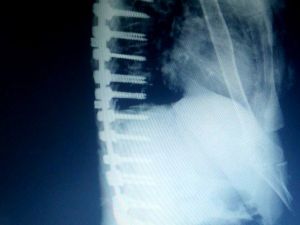

Edremit’te Bir Hastaya Erimeyen Platinden Omurga Yapıldı